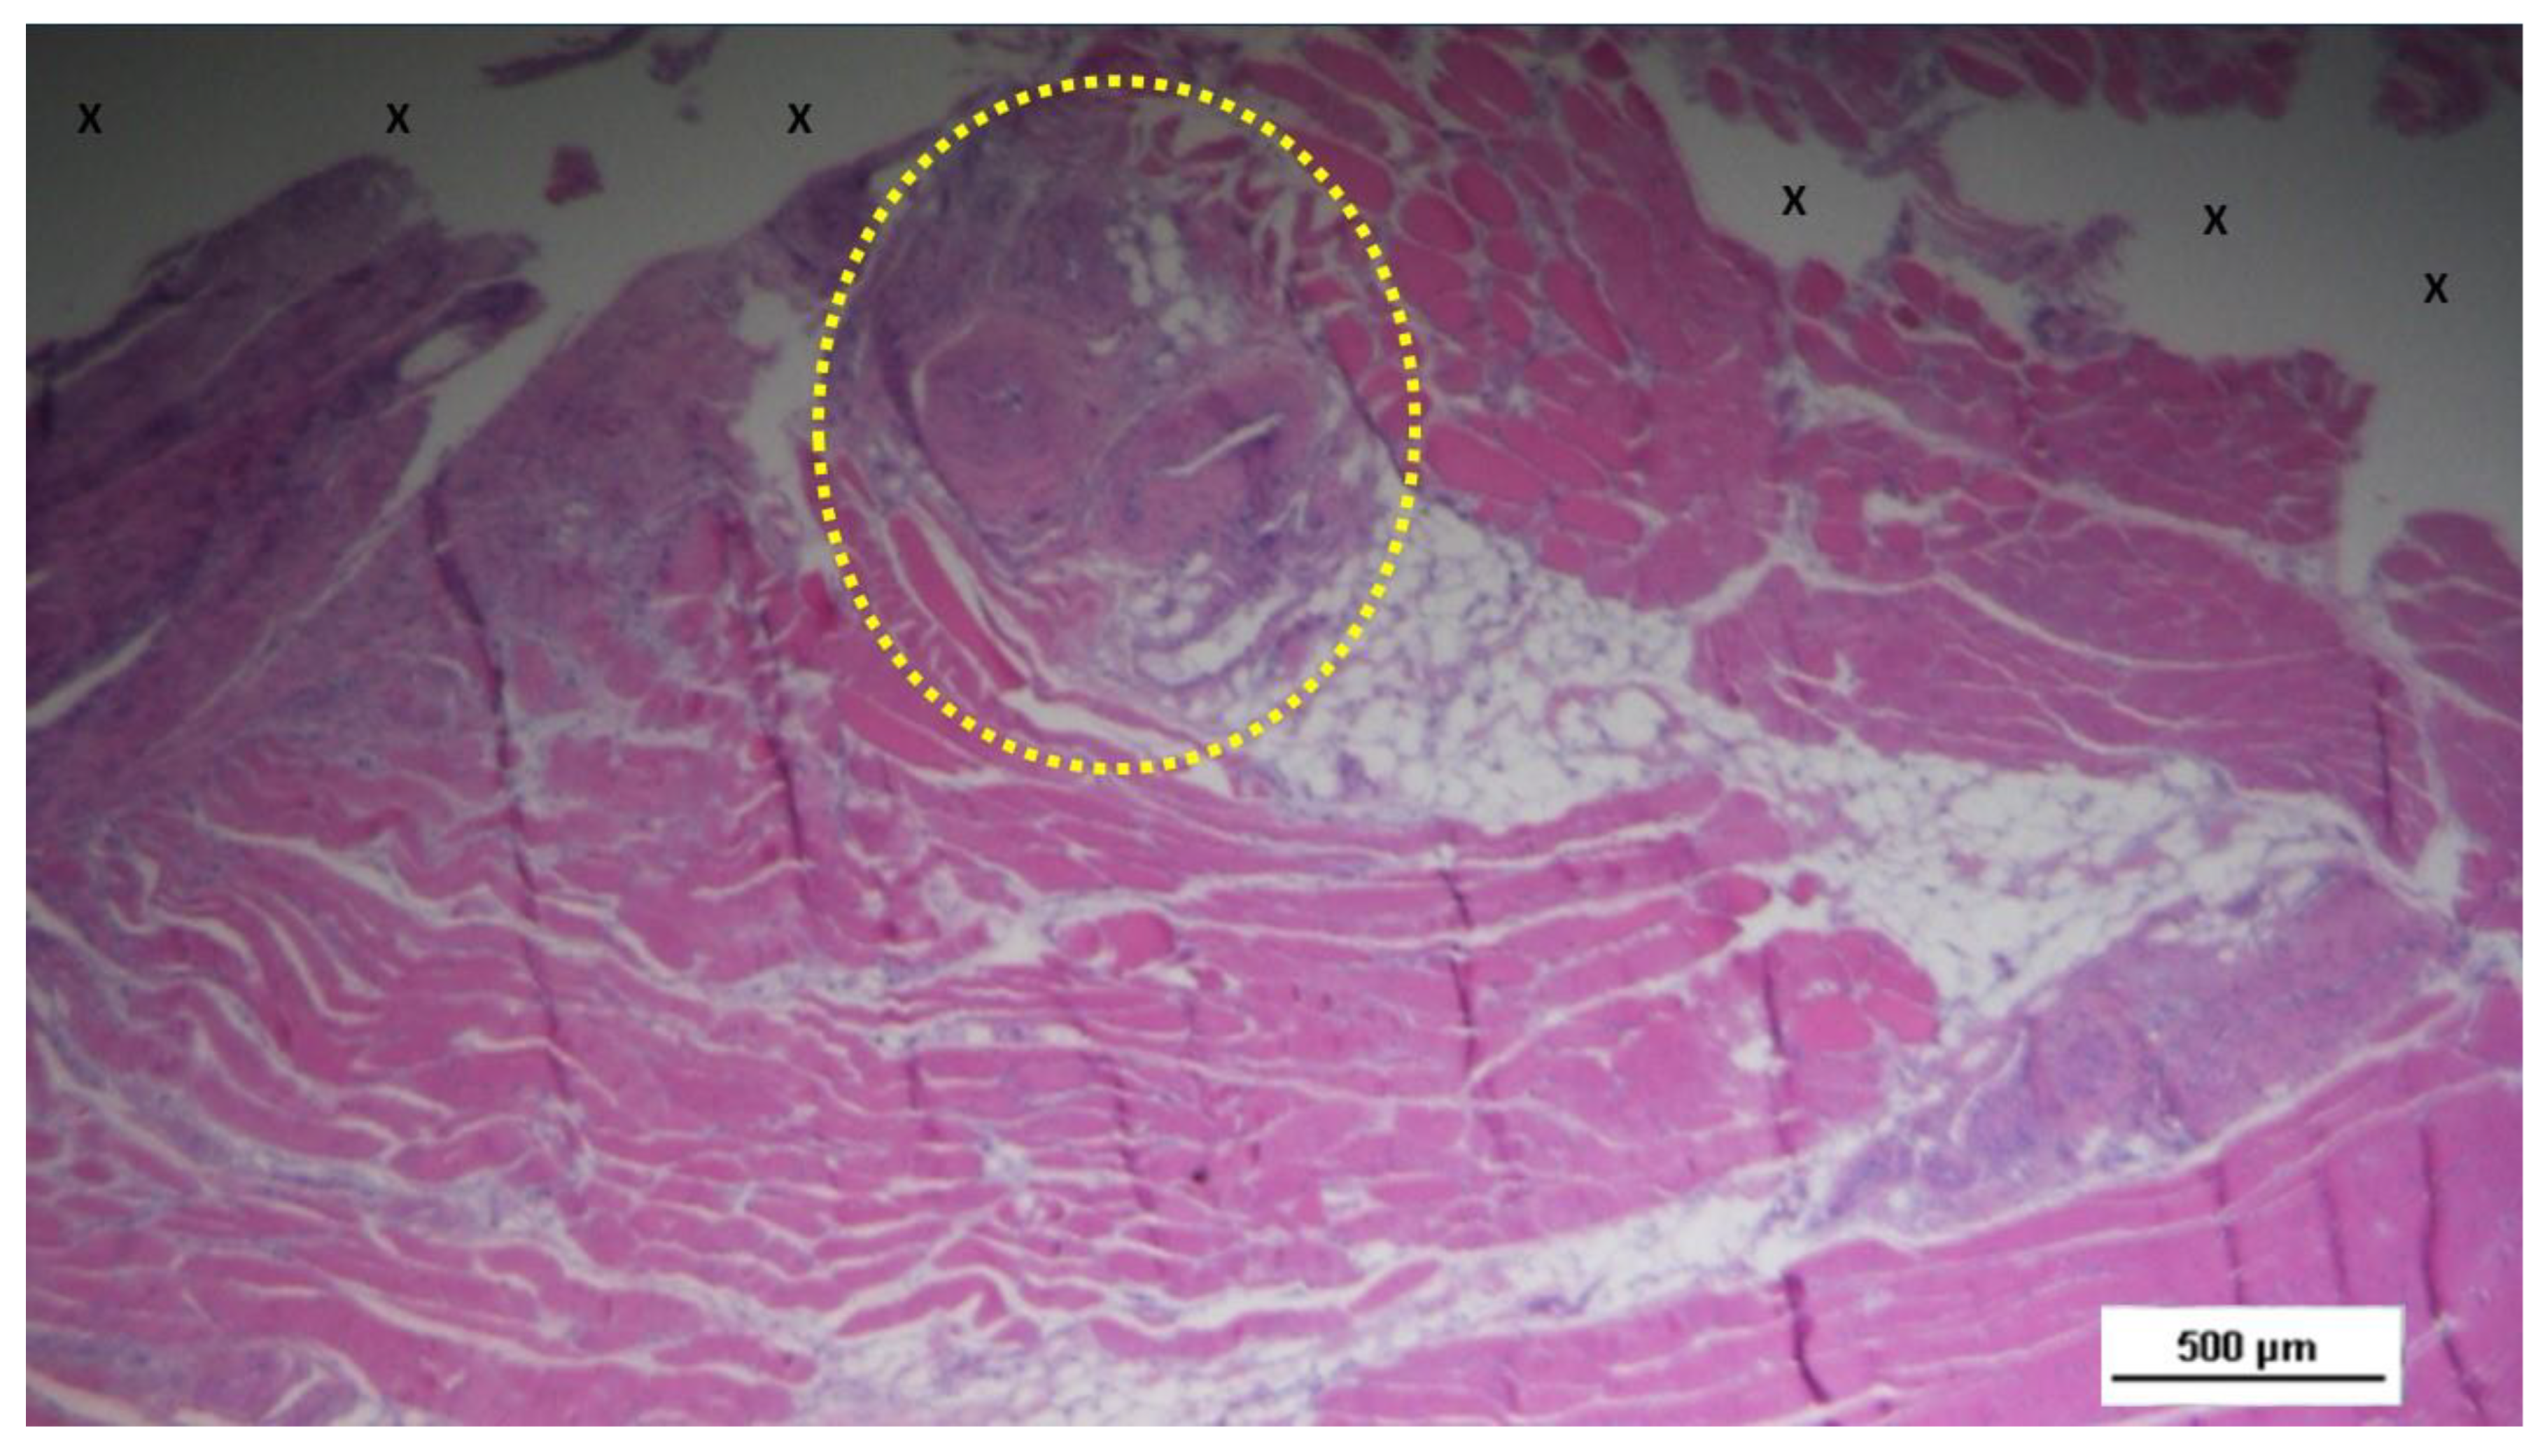

Figure 7.

Biopsy sample excised 3 months post-operation revealing a significant amount of muscle structures in advanced development, arranged in bundles (red elongated structures) near a large vascular element (yellow circle), in close proximity to the S&S fabric (X). HE 25X.

The development of muscle elements in biopsy samples taken from the 3D scaffold of the S&S device 3 to 4 months after placement (mid-term) showed a noticeable increase in both quantity and quality. At this stage, a greater number of muscle element clusters, along with extensive areas of muscle bundles, were observed adjacent to the device fabric and interspersed within well-organized connective tissue (

The muscle bundles showed in a stage of progressive development, with myocytes displaying spindle-formed contours, small nuclei, and eosinophilic cytoplasm. These features are characteristic of the evolving phase of muscle structure formation. [

26]